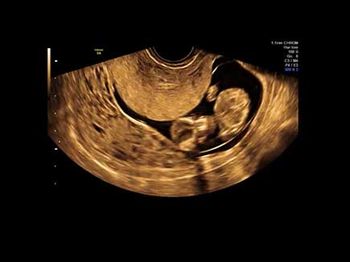

Challenge your diagnostic skills: Can you identify this anomaly?

Challenge your diagnostic skills: Can you identify this well-known anomaly?

Challenge your diagnostic skills: Can you identify this cardiac defect?